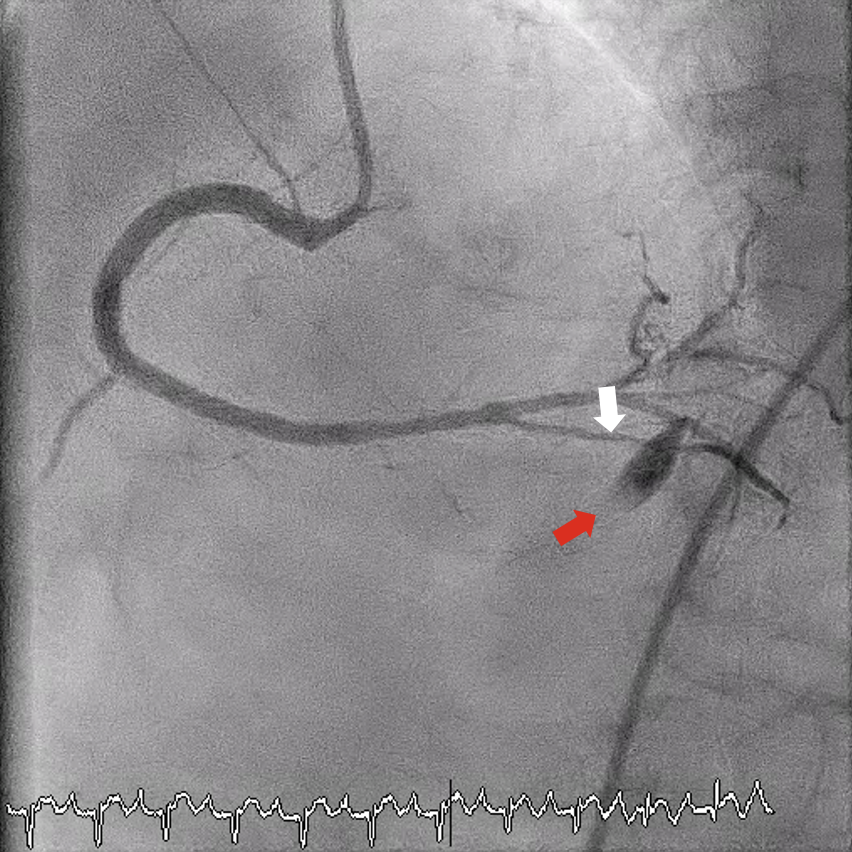

Excimer laser coronary atherectomy (ELCA; 0.9-mm catheter, escalated to 80 mJ/mm²/80 Hz, 25 cycles) (Philips) was used to facilitate crossing. During ELCA, hypotension (85/50 mm Hg) and chest pain occurred, which were attributed to dissection with slow flow (Figure 2, Video 1). Sequential balloon dilatations restored flow and hemodynamics stabilized at approximately 120/80 mm Hg without inotropes. Intravascular ultrasound (IVUS)-guided treatment included a 2.0 × 30-mm SeQuent Please NEO drug-coated balloon (B. Braun) distally and 2 overlapping Coroflex ISAR NEO drug-eluting stents (B. Braun) (2.25 × 38 mm and 3.5 × 32 mm) proximally, with excellent final angiographic (Figure 3, Video 2) and IVUS results.